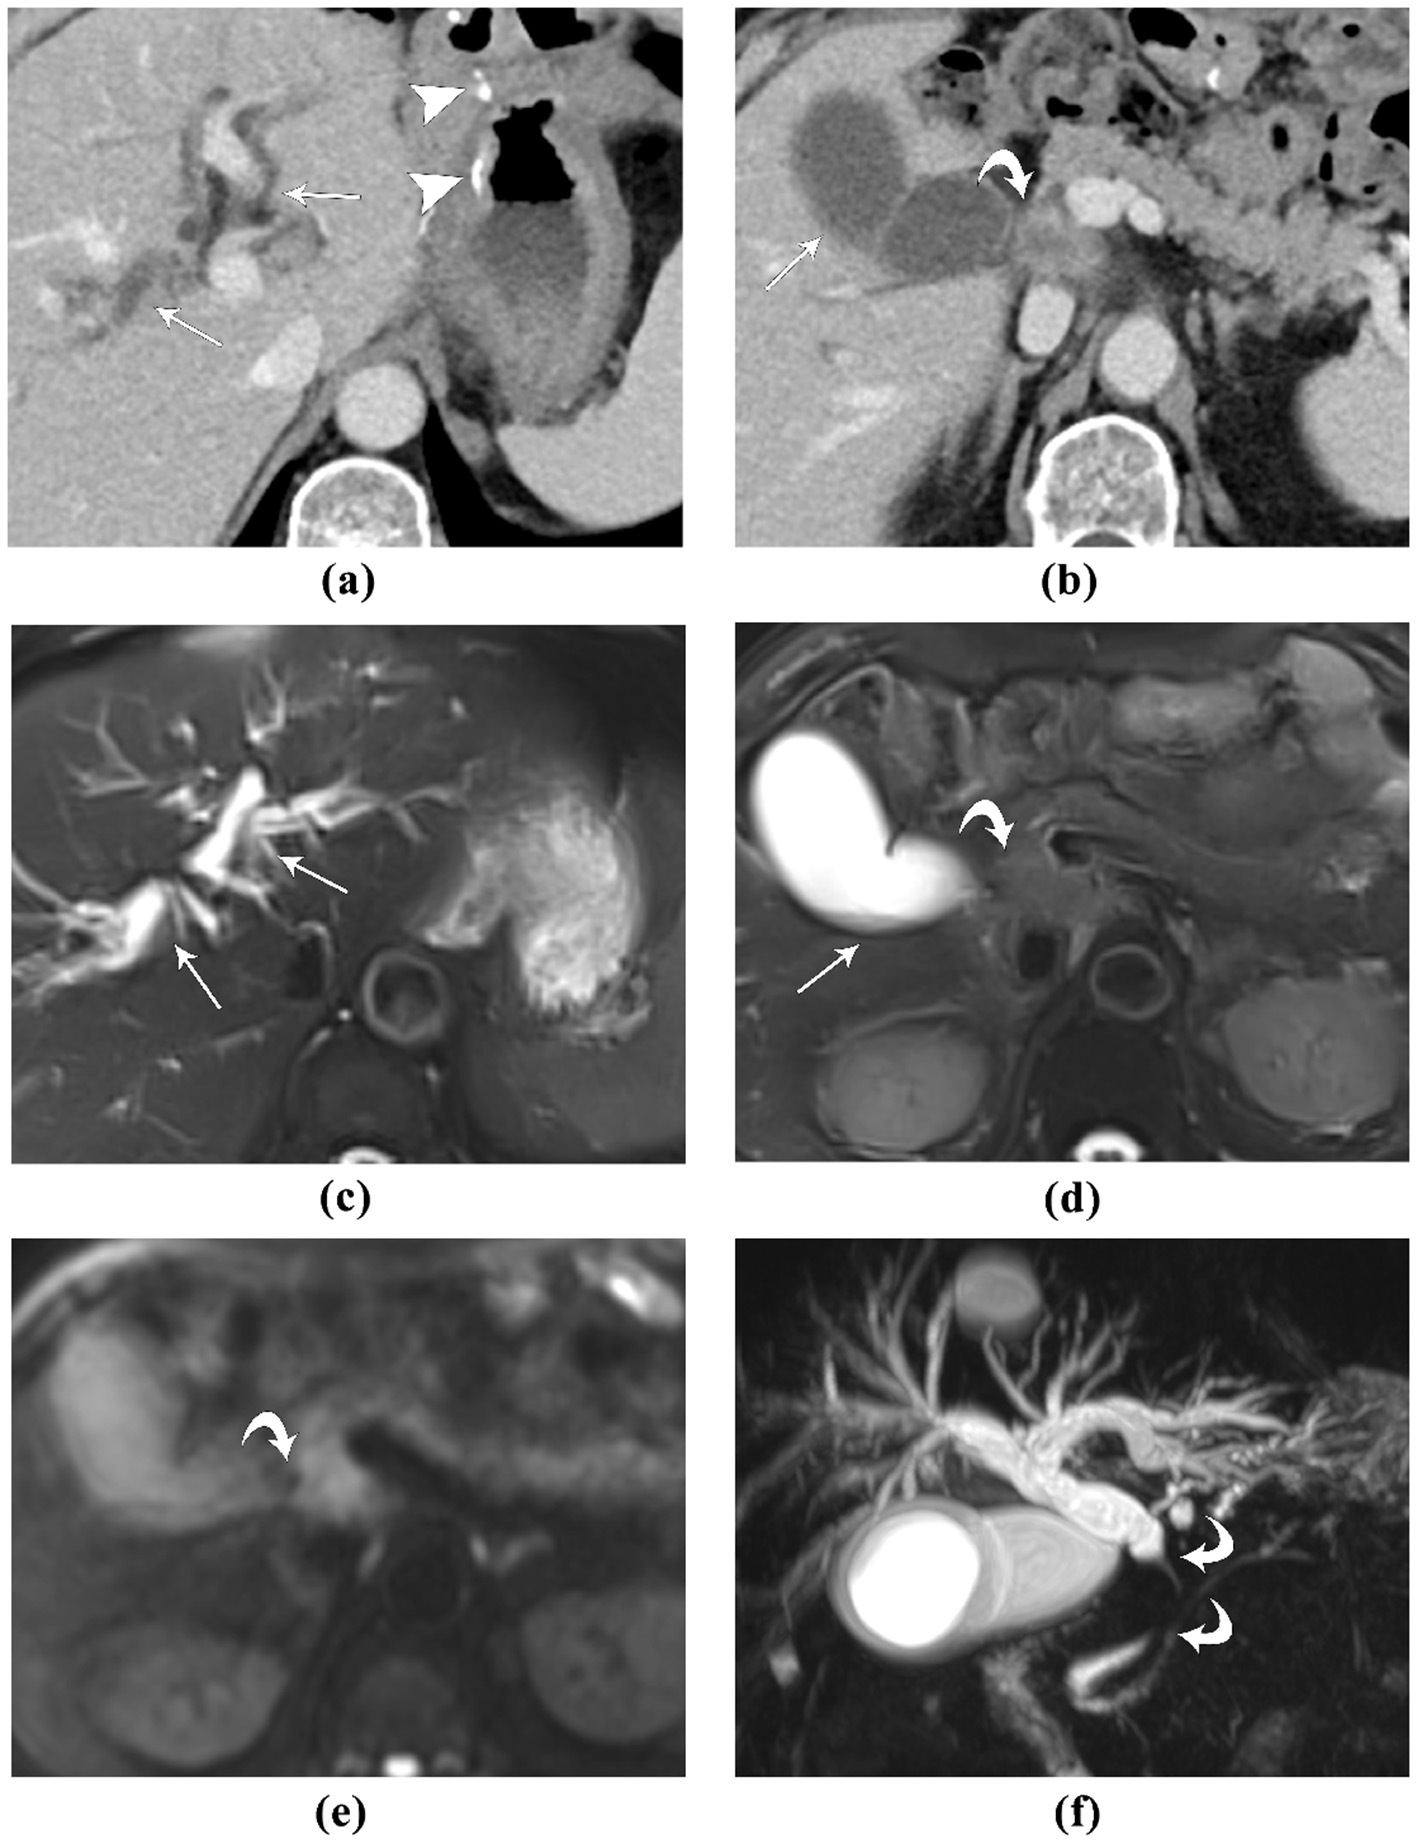

A 72-year-old male patient, who developed obstructive jaundice after 2 years of Bilroth II gastrectomy for gastric cancer: (A, B) contrast-enhanced CT, portal venous phase images. The high-density surgical sutures are seen (arrowhead). The lesion causing obstructive jaundice was initially missed. In retrospect, a soft-tissue mass with blurred margins and ring-like enhancement (curved arrow) is seen, which obstructs the extra-pancreatic extra-hepatic bile duct, causing the upstream biliary dilation (straight arrows); (C, D) MR T2-weighted fat-saturated images. The intra-hepatic bile ducts are dilated, and the gallbladder is distended with fluid-fluid level (straight arrows). The lesion causing obstructive jaundice was slightly hyper-intense to liver and pancreatic parenchyma (curved arrow); (E) MR diffusion-weighted image, the lesion was hyper-intense, suggestive of diffusion restriction. (F) MR cholangiopancreatography clearly depicts the occlusion of the extra-pancreatic extra-hepatic bile duct, and the upstream biliary dilation. This patient was diagnosed with gastric cancer metastasis to the bile duct. MRI depicts the location and extent of the lesion more clearly than contrast-enhanced CT.